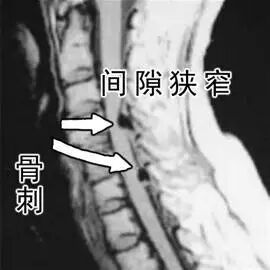

骨刺临床上称为骨质增生,多发于中年以上。这是因为随着年龄的增长,骨关节也会逐渐退化,当骨头与软组织接触的地方因长期承受压力、拉力、损伤,造成关节间的软骨渐渐失去水分与弹性,骨头与骨头磨损,人体为了减小骨关节之间的压力,在骨关节边缘上自然而然就会增生一部分来减少这个压力。它本质上是人体生理上的代偿功能,是人体为适应力的变化而产生的一种自我保护反应。

上班族每天对着电脑工作,身体长时间保持同一姿势,容易导致颈椎骨质增生。